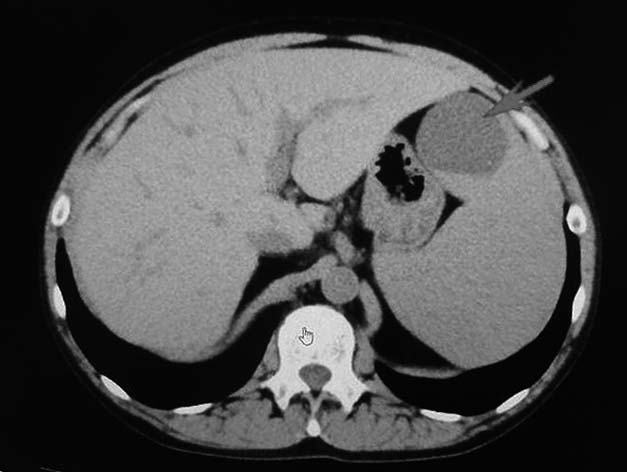

入院し精査. 骨髄はDry tap. CTでは脾腫が認められた. 末梢血には, 芽球, 幼若細胞の出現なし. 骨髄線維症よりもリンパ球系腫瘍が疑われた. 骨髄生検を行う.

腹部CT: 脾腫を認める. 脾腹側に4cm大の境界明瞭な腫瘤がみとめられ, 放射線科の診断はリンパ管腫などを疑うとされている.